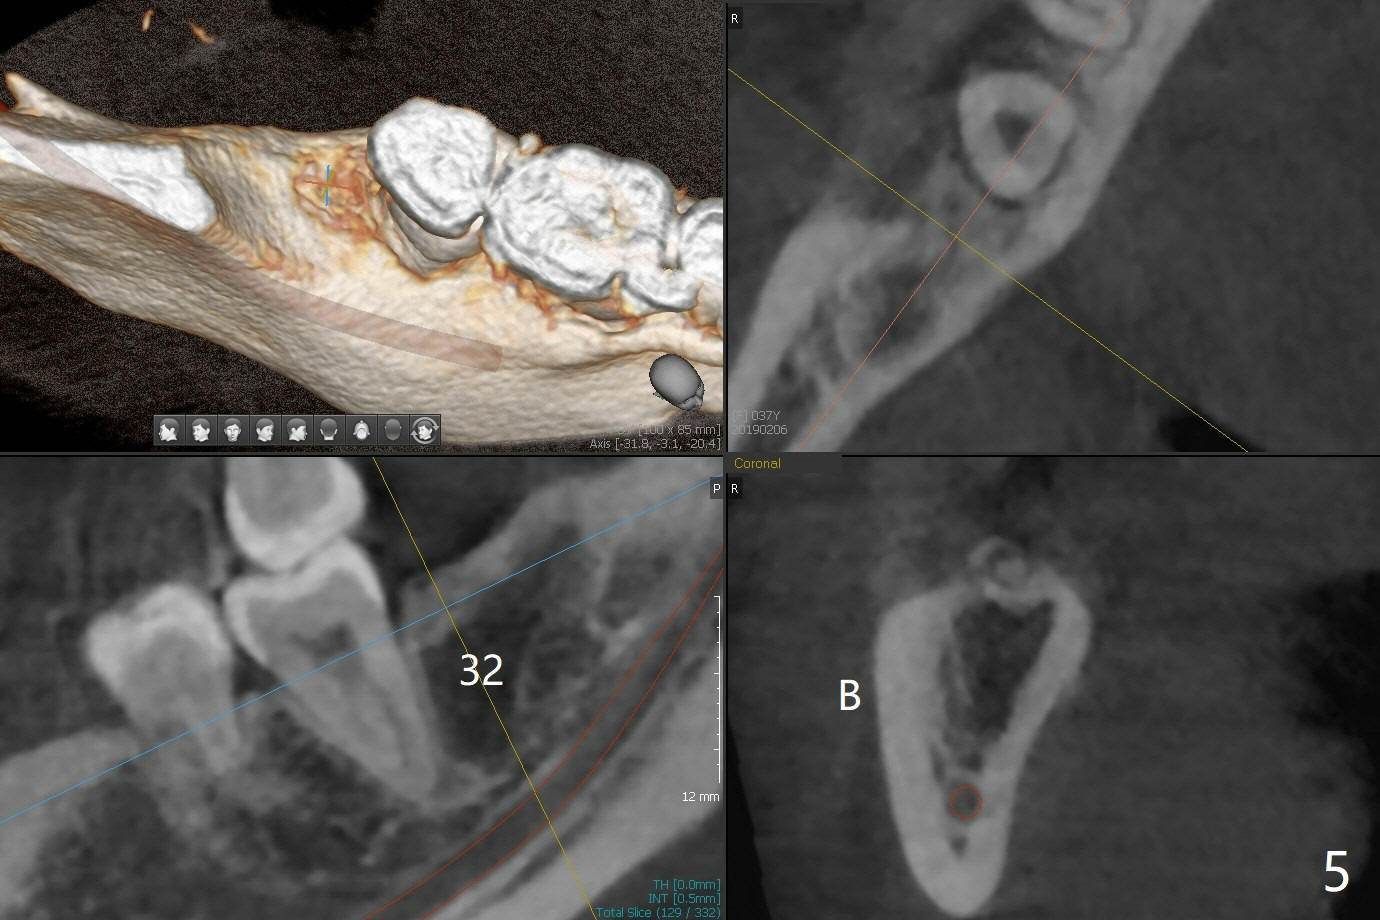

A 34-year-old lady requests extraction of #1, 16 and 32 (Fig.1). After incision for 32, surgical bur is used to create a purchase point to protect the thin bone between #31 and 32. The tooth is extracted with straight elevators and forceps. The socket is large single. Osteogen plug is placed with 4-0 plain gut suture (x4). There is cortical formation in the crest at #1, 16 and 32 three years postop (Fig.2-6 *, arrowheads). The advantage of Osteogen plug over Augma is easy placement with less risk of loss (by dissolving by saliva).